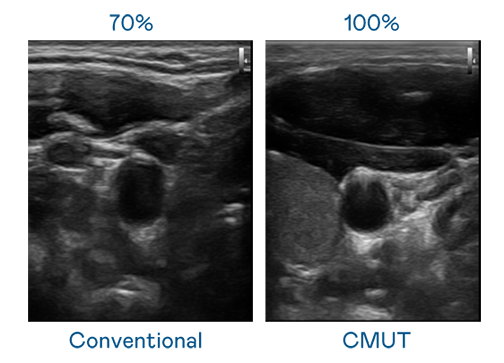

CMUT 技术是一种用电容式微机电元件来产生超音波讯号的技术。与传统 PZT 压电式技术相比,CMUT 频宽增加 30%,更宽频的超音波讯号让影像解析度大幅提升,是实现高影像品质医疗超音波扫描、促进精准医疗发展的关键技术。

超音波影像的解析度高低,首先取决于探头能发出的讯号频宽。利来 CMUT 可提供高清晰的超音波讯号,提供高频宽、高灵敏度、影像纹理细节更高的超音波影像,协助医护人员缩短影像判读时间及利用精准的医疗影像进行诊断。